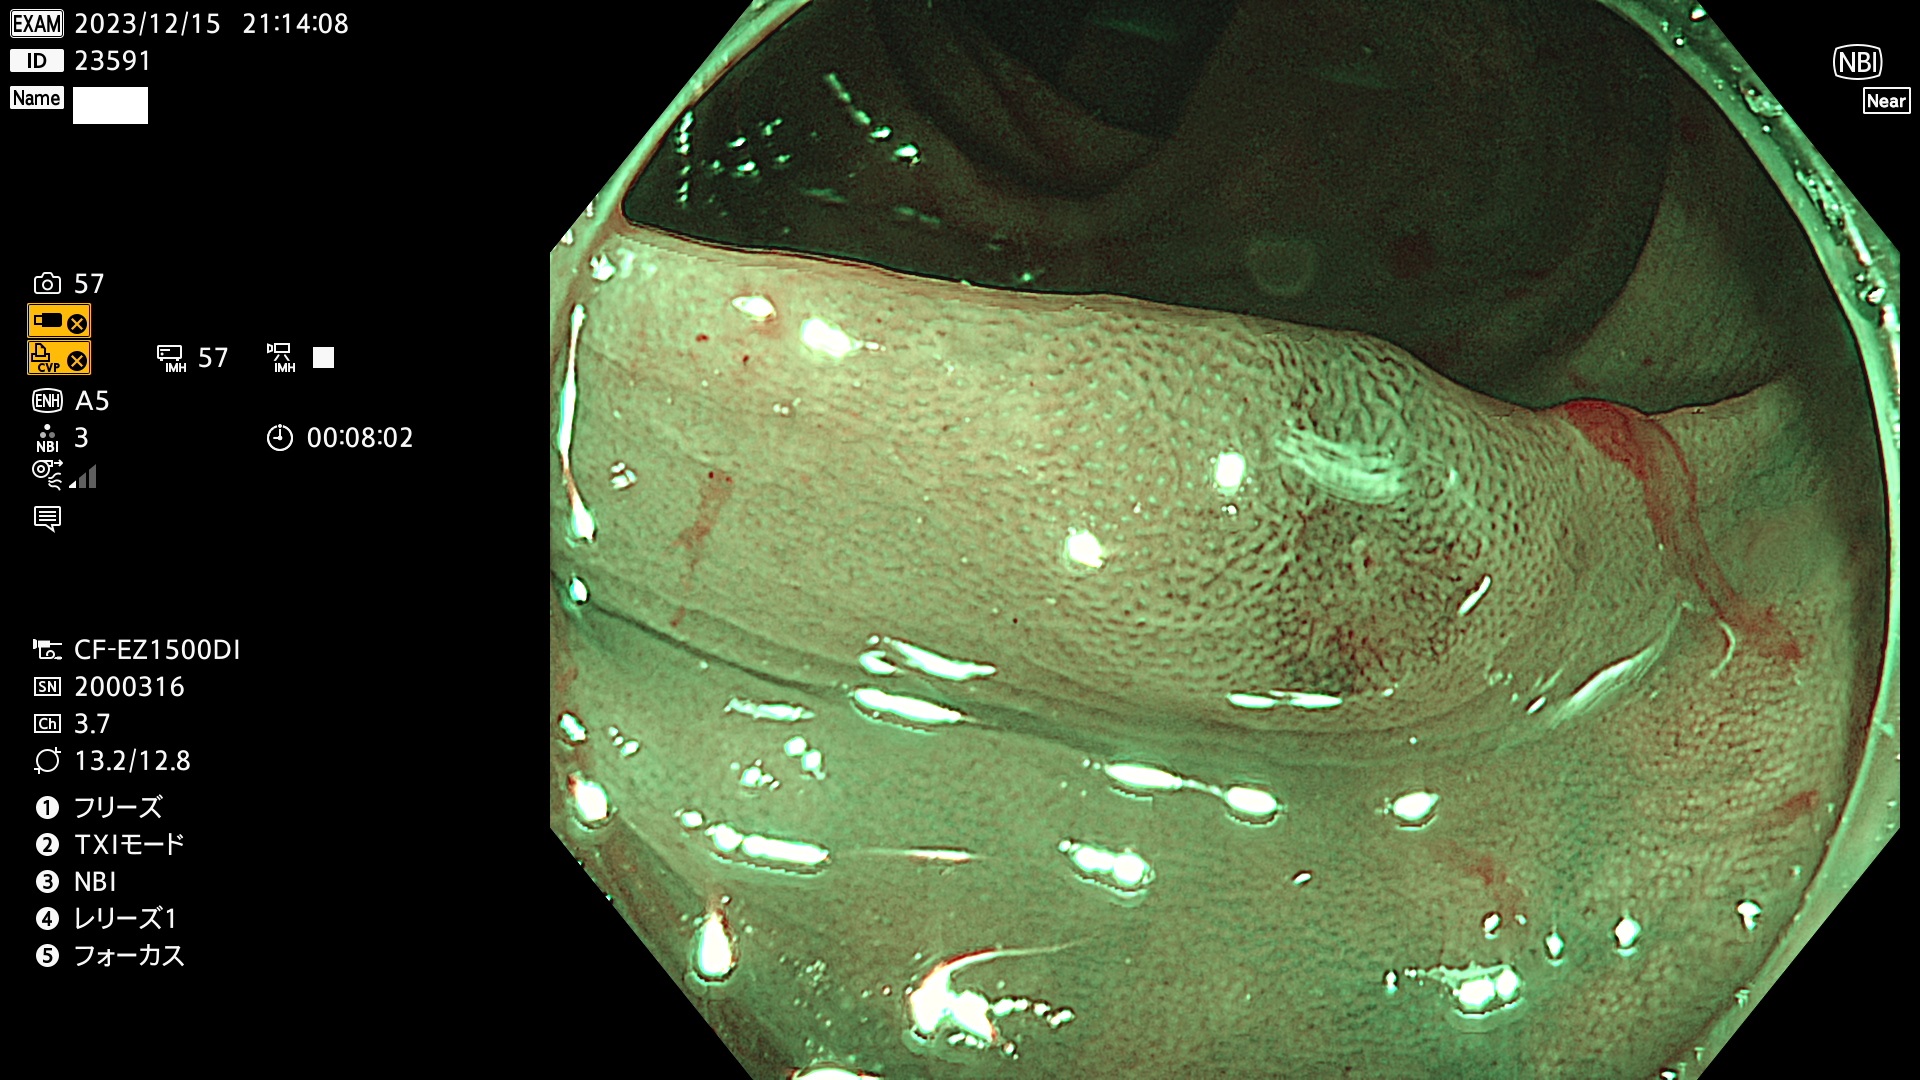

表面型腺腫(Flat Adenoma)の中で、完全に平坦な物をUb、陥凹している物をUcと呼びます。平坦隆起型(Ua)よりも、発見が難しく危険な病変です。このタイプは「内視鏡後・大腸癌の重要犯人」であり、この発見率は「腺腫発見率」よりも、重要な意味があります。

毎週の検査(木・金・土・日)に発見されたUb、Uc型・腺腫を、その週の日曜の夜にUPし1週間、提示します。

抽出の対象期間 2023年12月14日(木)〜12月18(日)の5日間(60件の検査)7件

当院で発見された炎症(ビラン)と紛らわしい腺腫